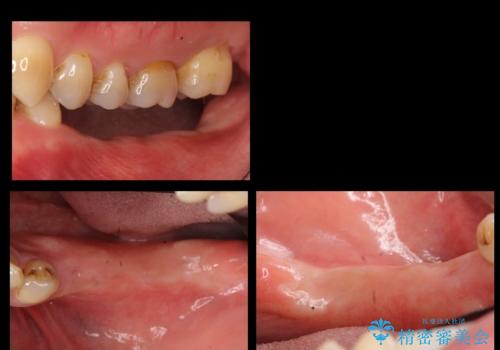

奥歯のインプラント 大人になって残っていた乳歯がダメになった

- 奥歯のブリッジの違和感を主訴に来院。

乳歯を使ってブリッジにしていましたが、支台歯が両方虫歯になっており、根が短くなって持たなくなった乳歯を抜いて、インプラントにすることになりました。